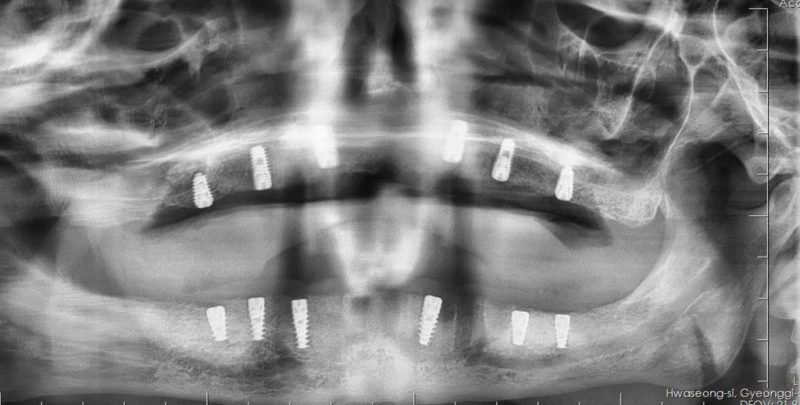

Cerrahi işlemin ardından hastanın üst ve alt çenesine implantlar yerleştirildi. Ameliyat sonrası genel durumunun stabil olduğu ve iyileşme sürecinin sorunsuz ilerlediği bildirildi.